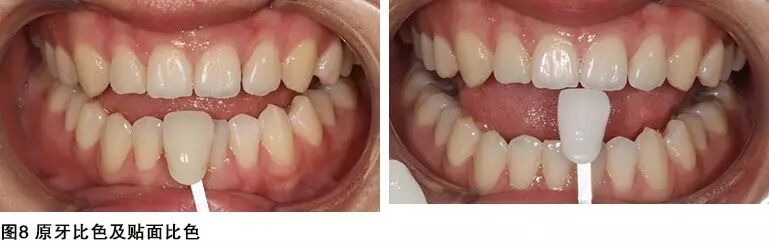

人们对牙齿健康和美容的要求越来越高,越来越多的用户开始选择微创甚至无创修复,这名患者也不例外,在进行了矫正治疗改变整个牙齿状况之后,最后的美学修复患者也要求不磨牙,因此为患者选择了美牙贴面修复,大大减少了牙齿的损伤,同时对颜色患者要求比较高,美女患者也希望修复的牙齿如明星般亮白闪耀。因此自己选择了好莱坞白,0M2美白改变颜色。